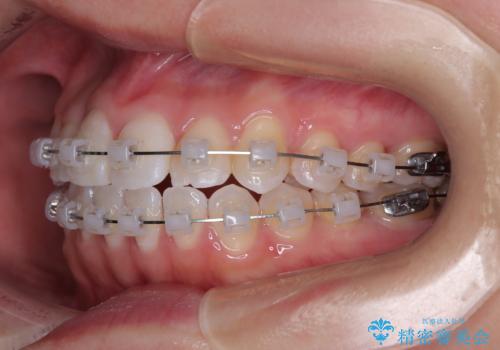

- クリアブラケット

- 1年1ヶ月

- 10-30回

ワイヤー矯正でもマウスピース矯正でも可能でしたが、短期間で、自身の手を煩わせることなく治療を行いたいとのことで、ワイヤー装置にて矯正治療を行うこととしました。